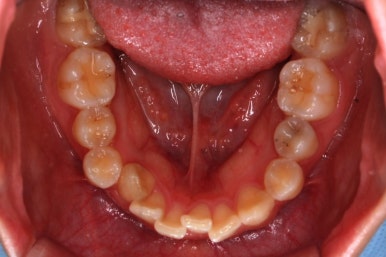

아랫니도 어느 정도 많이 가지런해졌습니다.

이제 아래쪽도 당겨 넣습니다.

원하는 만큼, 허락하는 만큼 계속 당겨 넣습니다. 연산동교정치과에서는 비발치 돌출입 교정을 위해 총 4개의 미니스크류를 식립했습니다.

치아는 매우 가지런해졌고, 과개교합도 개선이 되었으며 뻐드러진 앞니 각도도 정상적으로 회복이 되었습니다.

치아가 가지런해졌습니다.

뻐드러진 앞니가 정상적인 각도로 회복되었습니다.

전반적인 치아들의 위치가 뒤로 이동하였습니다.